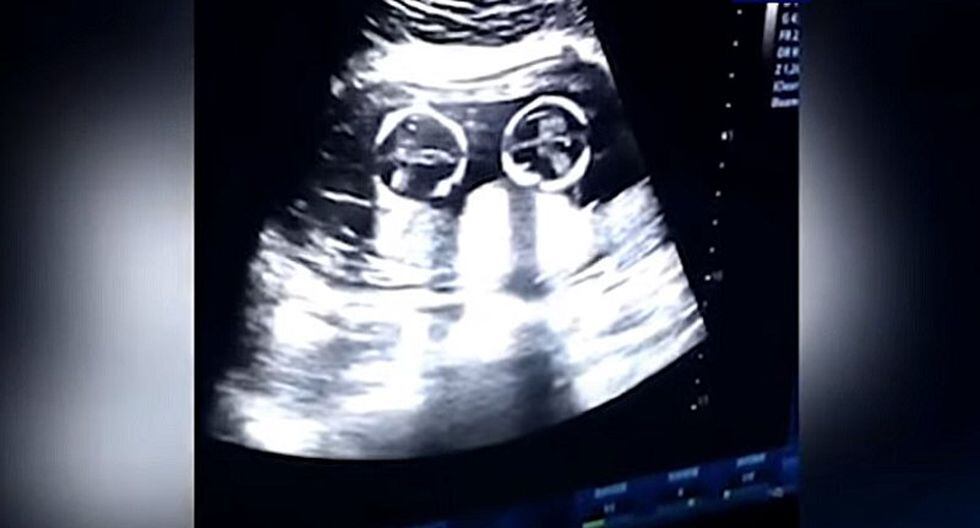

Un curioso video se ha viralizado en las redes sociales. En ella se puede ver lo que sería la "pelea" de unas gemelas dentro del útero de su madre.

El video fue captado durante la visita de rutina de la madre al doctor a los cuatro meses de gestación.

En las imágenes que circula en las redes parecería que las bebés están discutiendo, mientras su padre las graba desde el exterior.

Las gemelas fueron llamas Cherry y Strawberry y el video compartido ha sido reproducido más de 2,5 millones de veces.